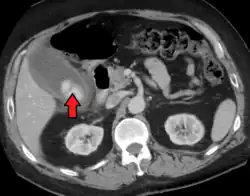

| Acute cholecystitis as seen on CT. Note the fat stranding around the enlarged gallbladder. | |

Right upper quadrant abdominal ultrasound is most commonly used to diagnose cholecystitis.[1][25][26] Ultrasound findings suggestive of acute cholecystitis include gallstones, pericholecystic fluid (fluid surrounding the gallbladder), gallbladder wall thickening (wall thickness over 3 mm),[27] dilation of the bile duct, and sonographic Murphy's sign.[13] Given its higher sensitivity, hepatic iminodiacetic acid (HIDA) scan can be used if ultrasound is not diagnostic.[13][14] CT scan may also be used if complications such as perforation or gangrene are suspected.[14]